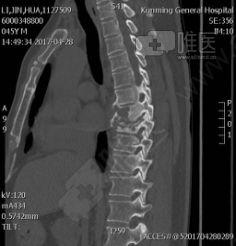

你有没有想过,当你的腰椎出了问题,医生会怎么帮你解决呢?今天,就让我带你走进一个神秘的世界——腰椎钉棒固定手术,看看医生们是如何用高科技手段,让你的腰杆重新挺直...